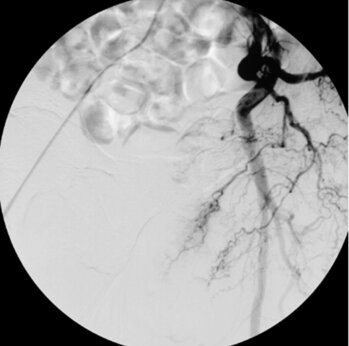

Digitale Subtraktionsangiografie: Blutaustritt aus zwei Dünndarmarterien (Aa. jejunales).

Digitale Subtraktionsangiografie: Nach Verschluss der zuführenden Arterien kamen die Darmblutungen zum Stillstand.